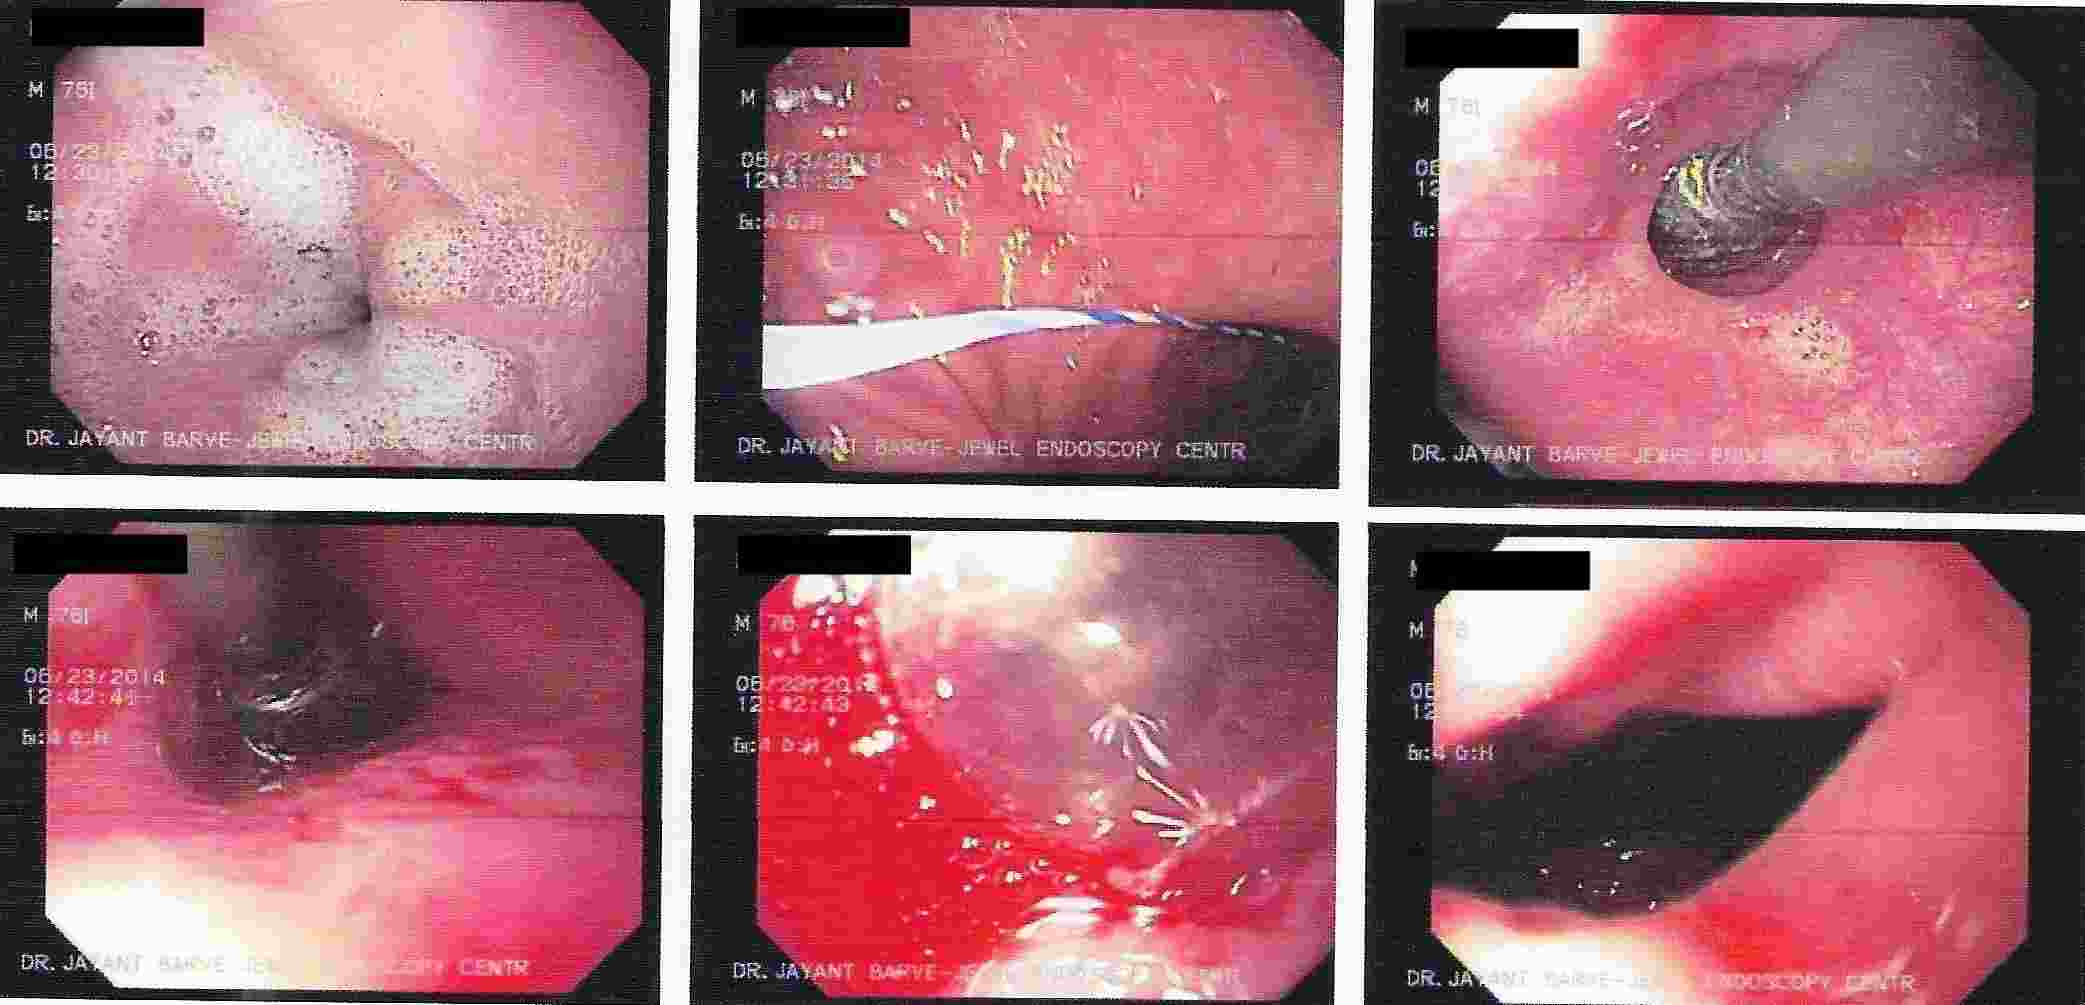

Strong contractions of the food pipe is known as dysmotility of esophagus and an unusual condition known

as Achalasia Cardia due to powerful contraction of the valve of the esophagus at its lower end which

can cause difficulty in swallowing.

Achalasia Cardia - Balloon Dilatation

Achalasia Cardia - Balloon Dilatation

Achalasia Cardia - Balloon Dilatation

Achalasia Cardia - Balloon Dilatation